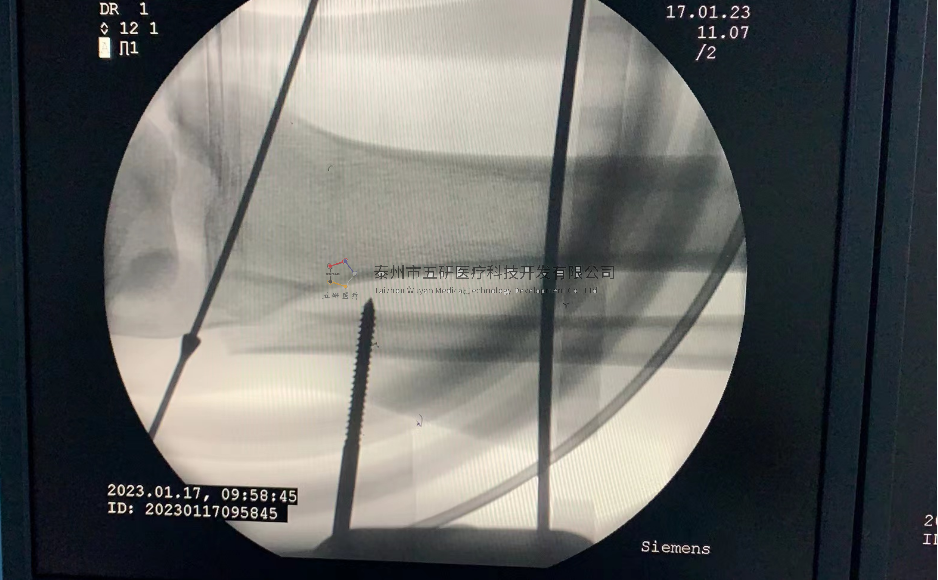

【患者情況】脛骨遠(yuǎn)端骨折伴腓骨骨折

【影像圖片—術(shù)前】

【影像圖片—術(shù)后】